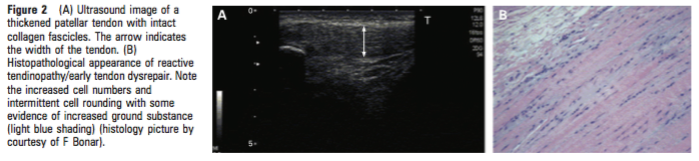

Quid de l’imagerie  (figure 2 et 3) ?

L’examen qui permet à ce jour de quantifier le plus précisément ce continuum est l’échographie. L’échographie permet de visualiser la structure du tendon et la présence de zones plus ou moins hypoechogènes, de quantifier son épaisseur, et grâce au doppler puissance, elle permet de déterminer la présence ou non de petits vaisseaux sanguins caractéristiques de la phase de remaniement avancée ou de la phase dégénérative.

Source : Cook et al 2009